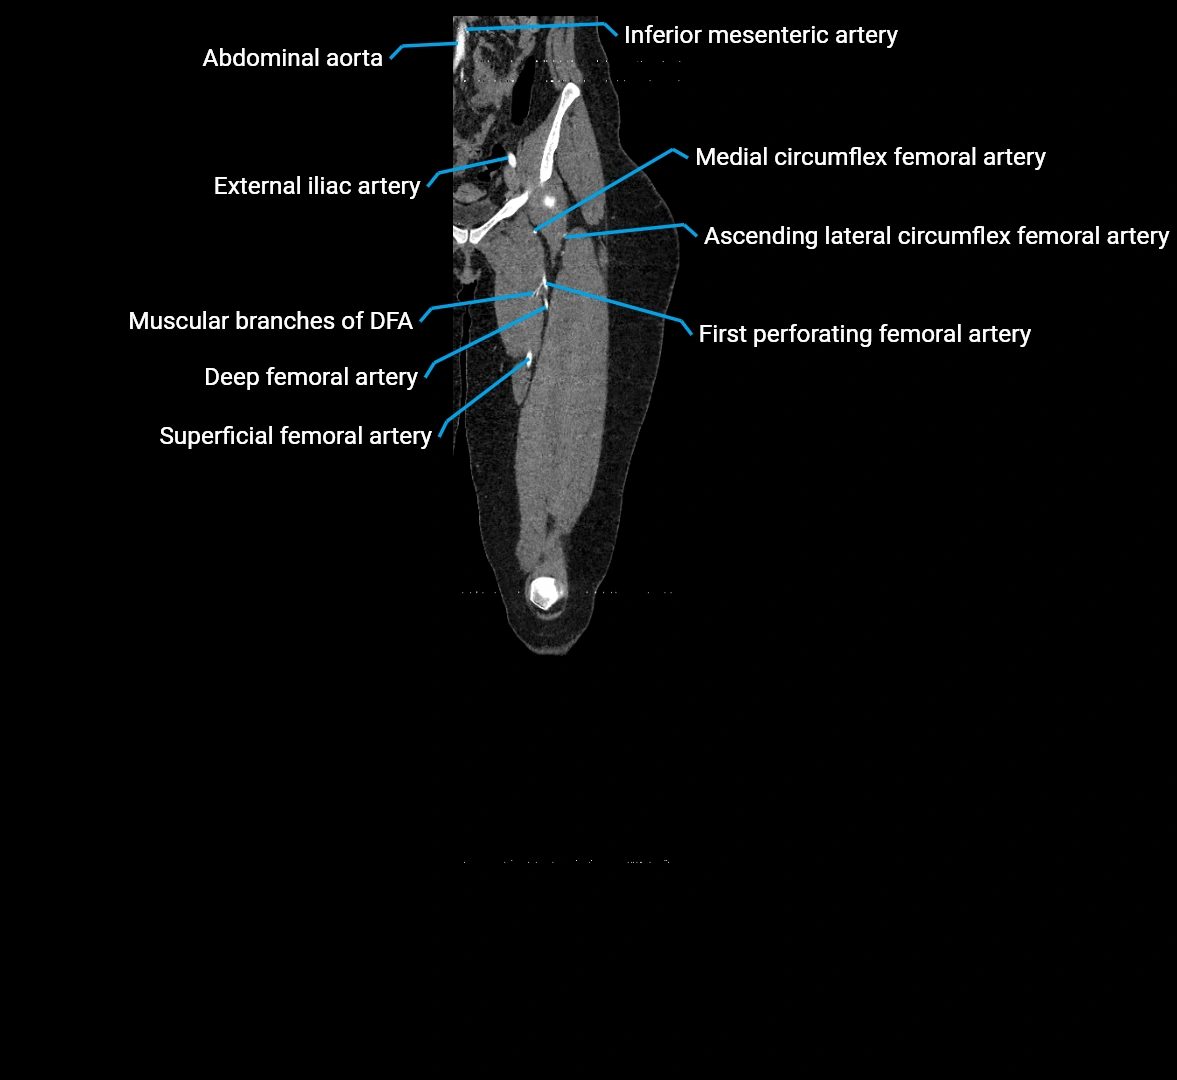

Branches

• Unpaired visceral branches: celiac trunk, superior mesenteric artery (SMA), inferior mesenteric artery (IMA)

• Paired visceral branches: middle suprarenal arteries, renal arteries, gonadal arteries (testicular or ovarian)

• Parietal branches: inferior phrenic arteries, lumbar arteries, median sacral artery

• Terminal branches: right and left common iliac arteries

Contrast-enhanced CT (CTA):

• Gold standard for abdominal aortic imaging

• Provides excellent detail of lumen, wall, aneurysm, thrombus, and branch vessels

• Multiplanar and 3D reconstructions help in aneurysm measurement, stent graft planning, and dissection evaluation

• Detects acute rupture, traumatic injury, or occlusion with high sensitivity